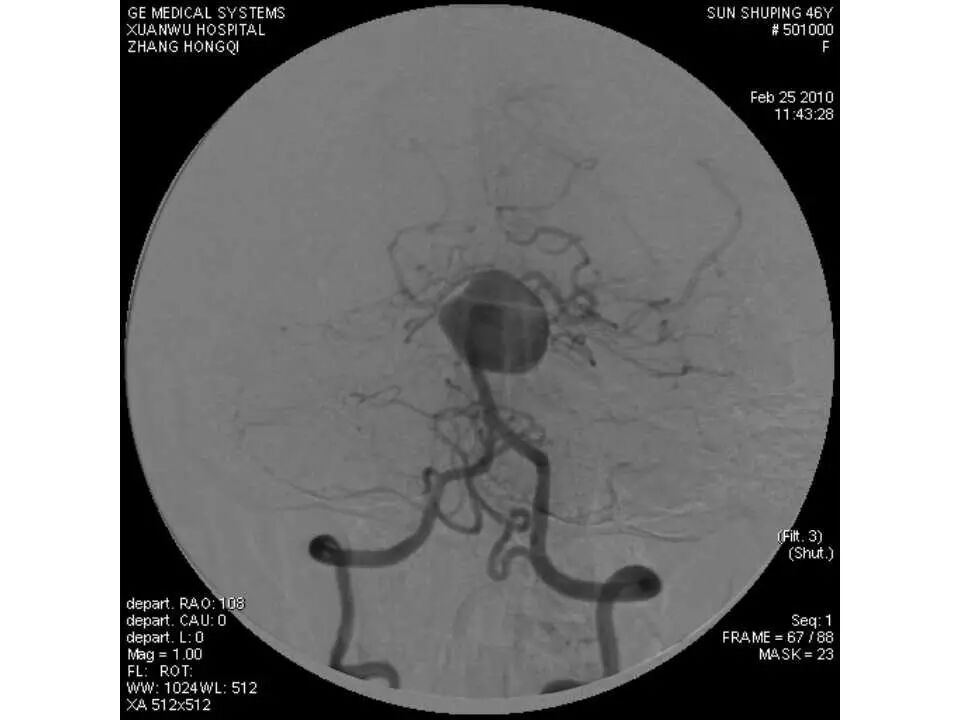

今天为大家分享的是“强生医疗CNV-神经介入专栏”第十五期,由首都医科大学宣武医院何川教授带来的“颅内动脉瘤介入治疗”精彩讲课视频及PPT,欢迎观看、阅读。文章仅代表作者个人观点,如有不同见解,欢迎同道斧正!

何川 ,首都医科大学宣武医院副主任医师,中国医师协会神经介入专业委员会常务委员,长期从事脑血管病和脊髓血管病的手术及介入治疗和相关研究工作。首都医科大学神经外科博士,师从于中国神经介入开创人凌锋教授;日本东北大学医院脑血管病治疗科博士后,师从于日本国脑血管病血管内治疗的开创者高桥教授。